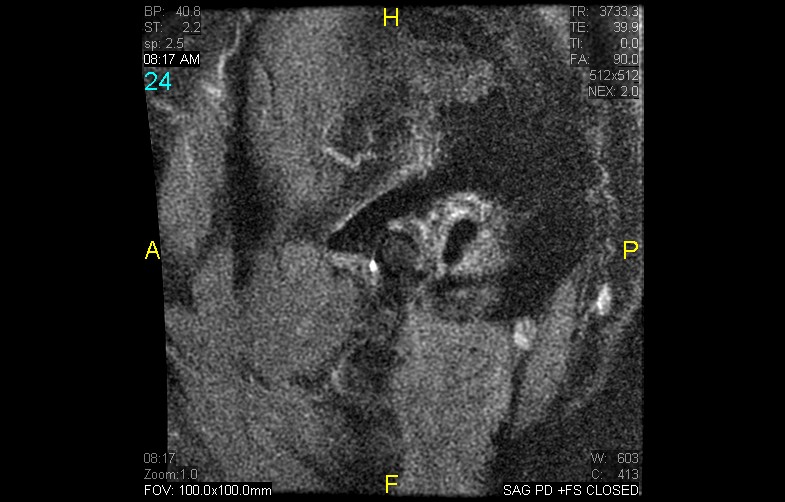

Courtesy